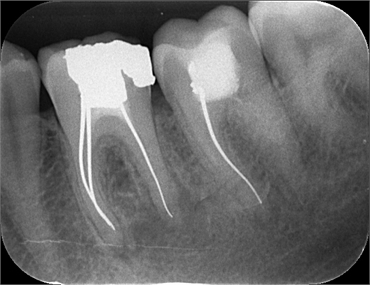

One of the earliest obturating materials were silver points. Silver possesses antimicrobial properties and is easily distinguished on a radiograph. It was first introduced in 1933 by E.A. Jasper. The material introduced by Jasper was stiff, and thus used in narrow & tortuous root canals. It was also easy to handle and placement within thin canals was much easier.

Another disadvantage was that the stiffness of silver points did not allow them to snugly fit within the canal space. A liquid material called a sealer is used to adhere the silver points. Secondly, the silver points do not seal the canal space in all three dimensions. This leads to poor fitting of the silver points, resulting in voids that can be invaded by microbes. The lower third of the root canal is rarely sealed, and hence, chances of re-infection are high.

The American Association of Endodontists no longer recommend silver points as obturating materials. The cytotoxic silver salts released upon corrosion is a major factor in it being derailed from modern endodontic practice. Yet, knowledge of silver points is important as dentists frequently encounter cases where obturation was done with silver points. In these cases, it is important to educate the patient about silver points and how retreatment with a better material like gutta-percha can avoid further derailing of the tooth's condition. An assessment of the tooth and its surrounding bony architecture must be done with radiographs before opting for a root canal treatment again.